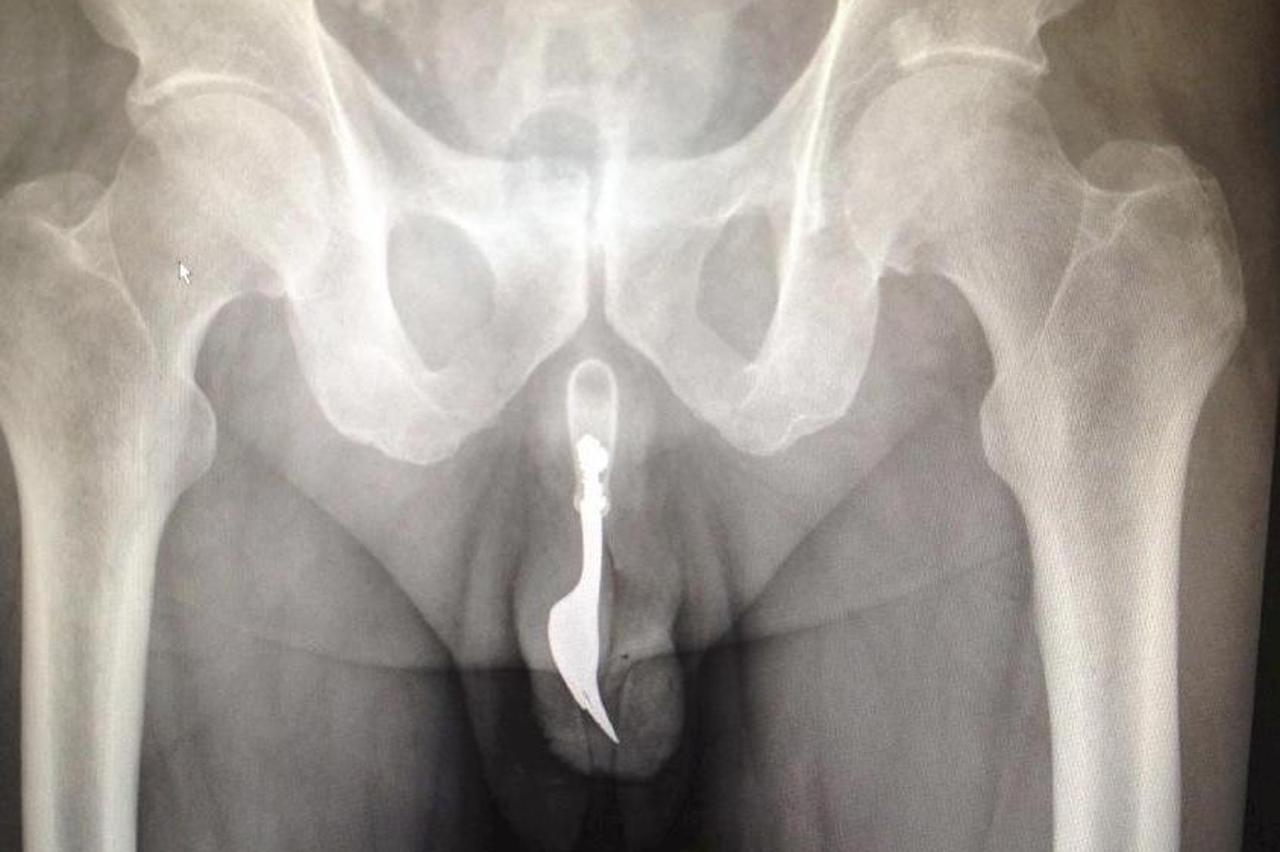

Nije mogao izvaditi Seksualno zadovoljavanje!? Ugurao si vilicu u penis International Journal of Surgery Case Reports napisao je da si je 70-godišnjak vilicu ugurao zbog seksualnog zadovoljstva. Ostaje nejasno kako se želio seksualno zadovoljiti guranjem vilice u penis.